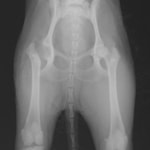

術後レントゲン